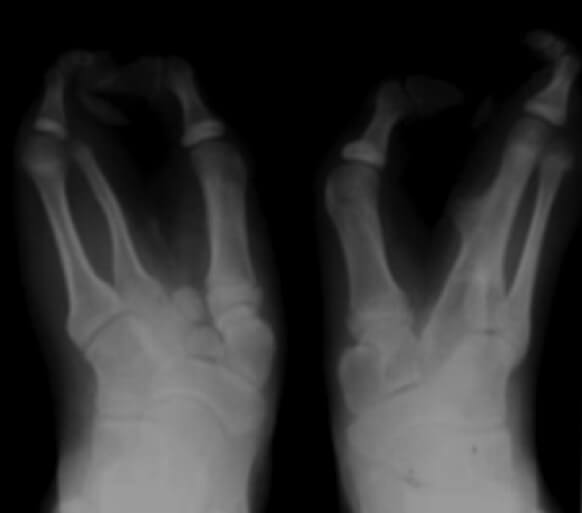

En la radiografía simple se observa, en la mano izquierda, fusión del segundo y tercer metacarpiano, con ausencia de las falanges del dedo medio. En la derecha, agenesia del primer metacarpiano, con segundo a quinto sin alteraciones, agenesia de la falange proximal del índice y medio, y ausencia de sus respectivas falanges media y distal. Mientras que en ambos pies se evidencia la ausencia de múltiples metatarsianos y falanges (Figura 3 y 4).

Figura 3. Radiografía anteroposterior de ambas manos.